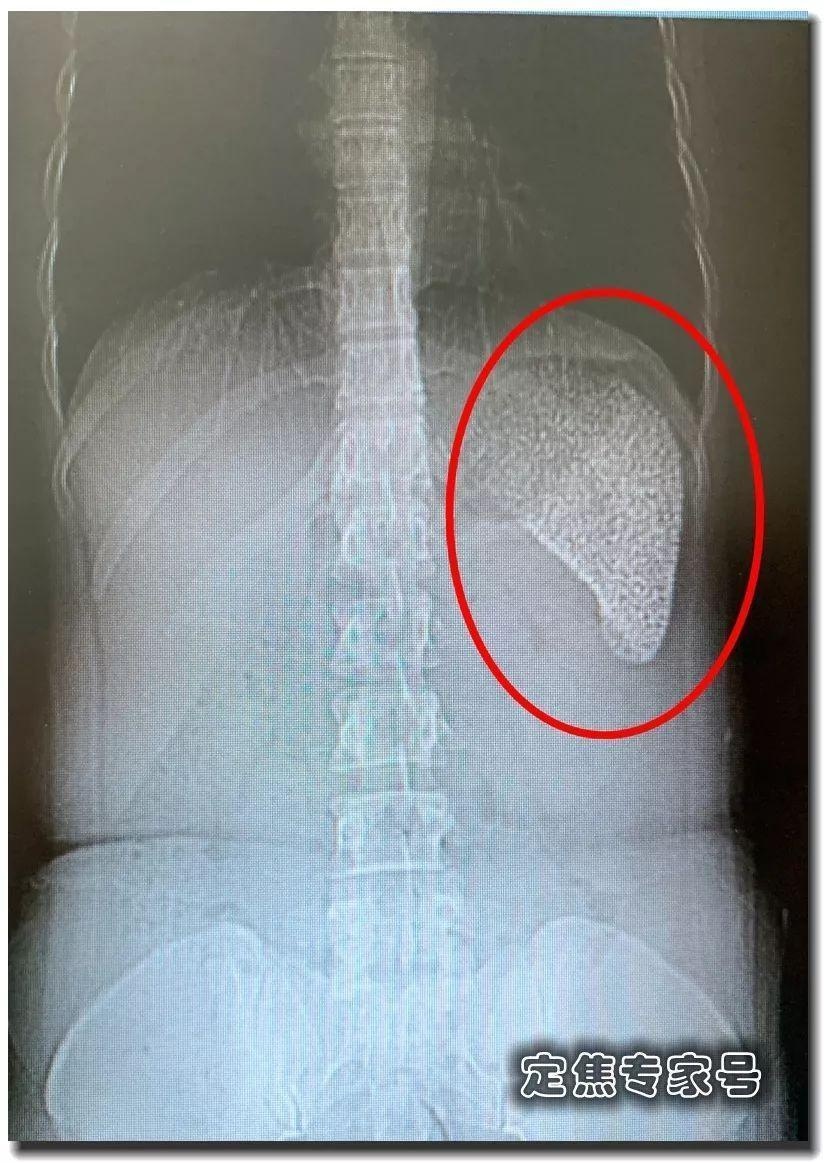

Qua phim chụp cắt lớp, ông nhận thấy lá lách của Hà có dấu hiệu lạ. Thông thường, những tạng rỗng khi lên phim sẽ có màu đen, tạng đặc sẽ có màu trắng. Lá lách là tạng rỗng nhưng lại có màu trắng rất rõ ràng và bằng mắt thường có thể thấy toàn bộ lá lách là những hạt vôi hóa hoặc sỏi cứng.

| Lá lách của Hà Lợi Lợi trên phim chụp CT. Ảnh: Sohu. |

Đối với GS Lý, đây là trường hợp đầu tiên ông gặp có biểu hiện lâm sàng như vậy, nó không giống khối ung thư, không phải nhiễm trùng hay ổ hoại tử. Ông quyết định tiến hành phẫu thuật lá lách để có hướng điều trị chính xác.